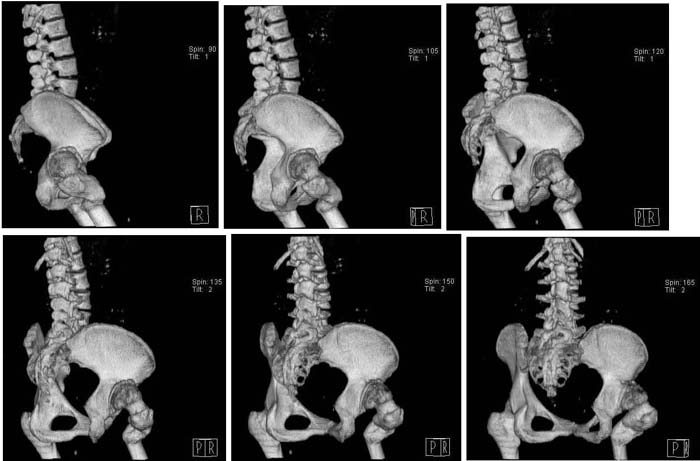

Уважаемые коллеги!Женщина, 35 летВ прошлом по поводу врожденного вывиха бедра перенесла операцию остеотомии по Шанцу

с удлинением правой ноги за счет бедра на уровне диафиза. В последнее время прогрессируют боли в правом тазобедренном суставе, порочное положение правой ноги, затруднена ходьба.Вопросы:1) Целесообразно ли эндопротезирование правого тазобедренного сустава?2) Целесообразный ли следующие действия: канал бедренной кости предполагаем вскрыть для введения ножки протеза на высоте угловой деформации, предполагаем низведение большого вертела с мышцами; протез будет подобран индивидуально, предполагается умеренная версия?В приложении рентгенограммы и трехмерная КТ.В цветном и более качественном варианте КТ размещена здесь